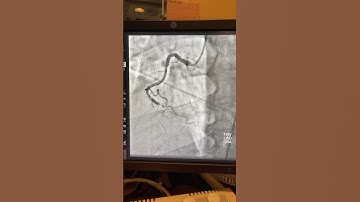

Case 96: Manual of CTO Interventions: Confluent balloon and CART technique